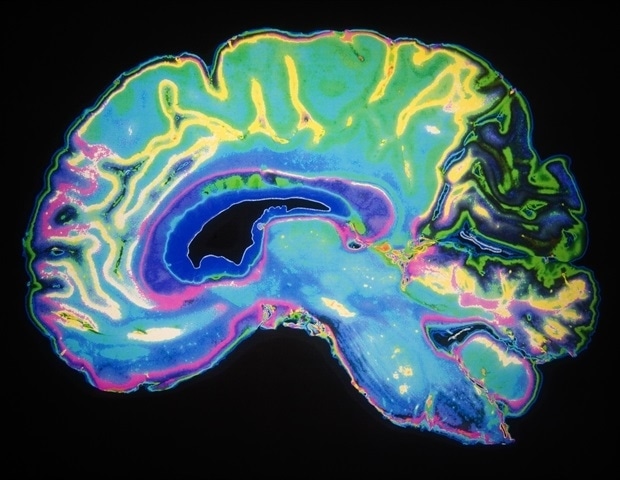

An international team led by researchers at Baylor College of Medicine, Texas Children’s Hospital, McGill University and University of Pittsburgh School of Medicine has discovered what drives the growth of a lethal pediatric brain tumor called Posterior Fossa Type A (PFA) ependymoma.